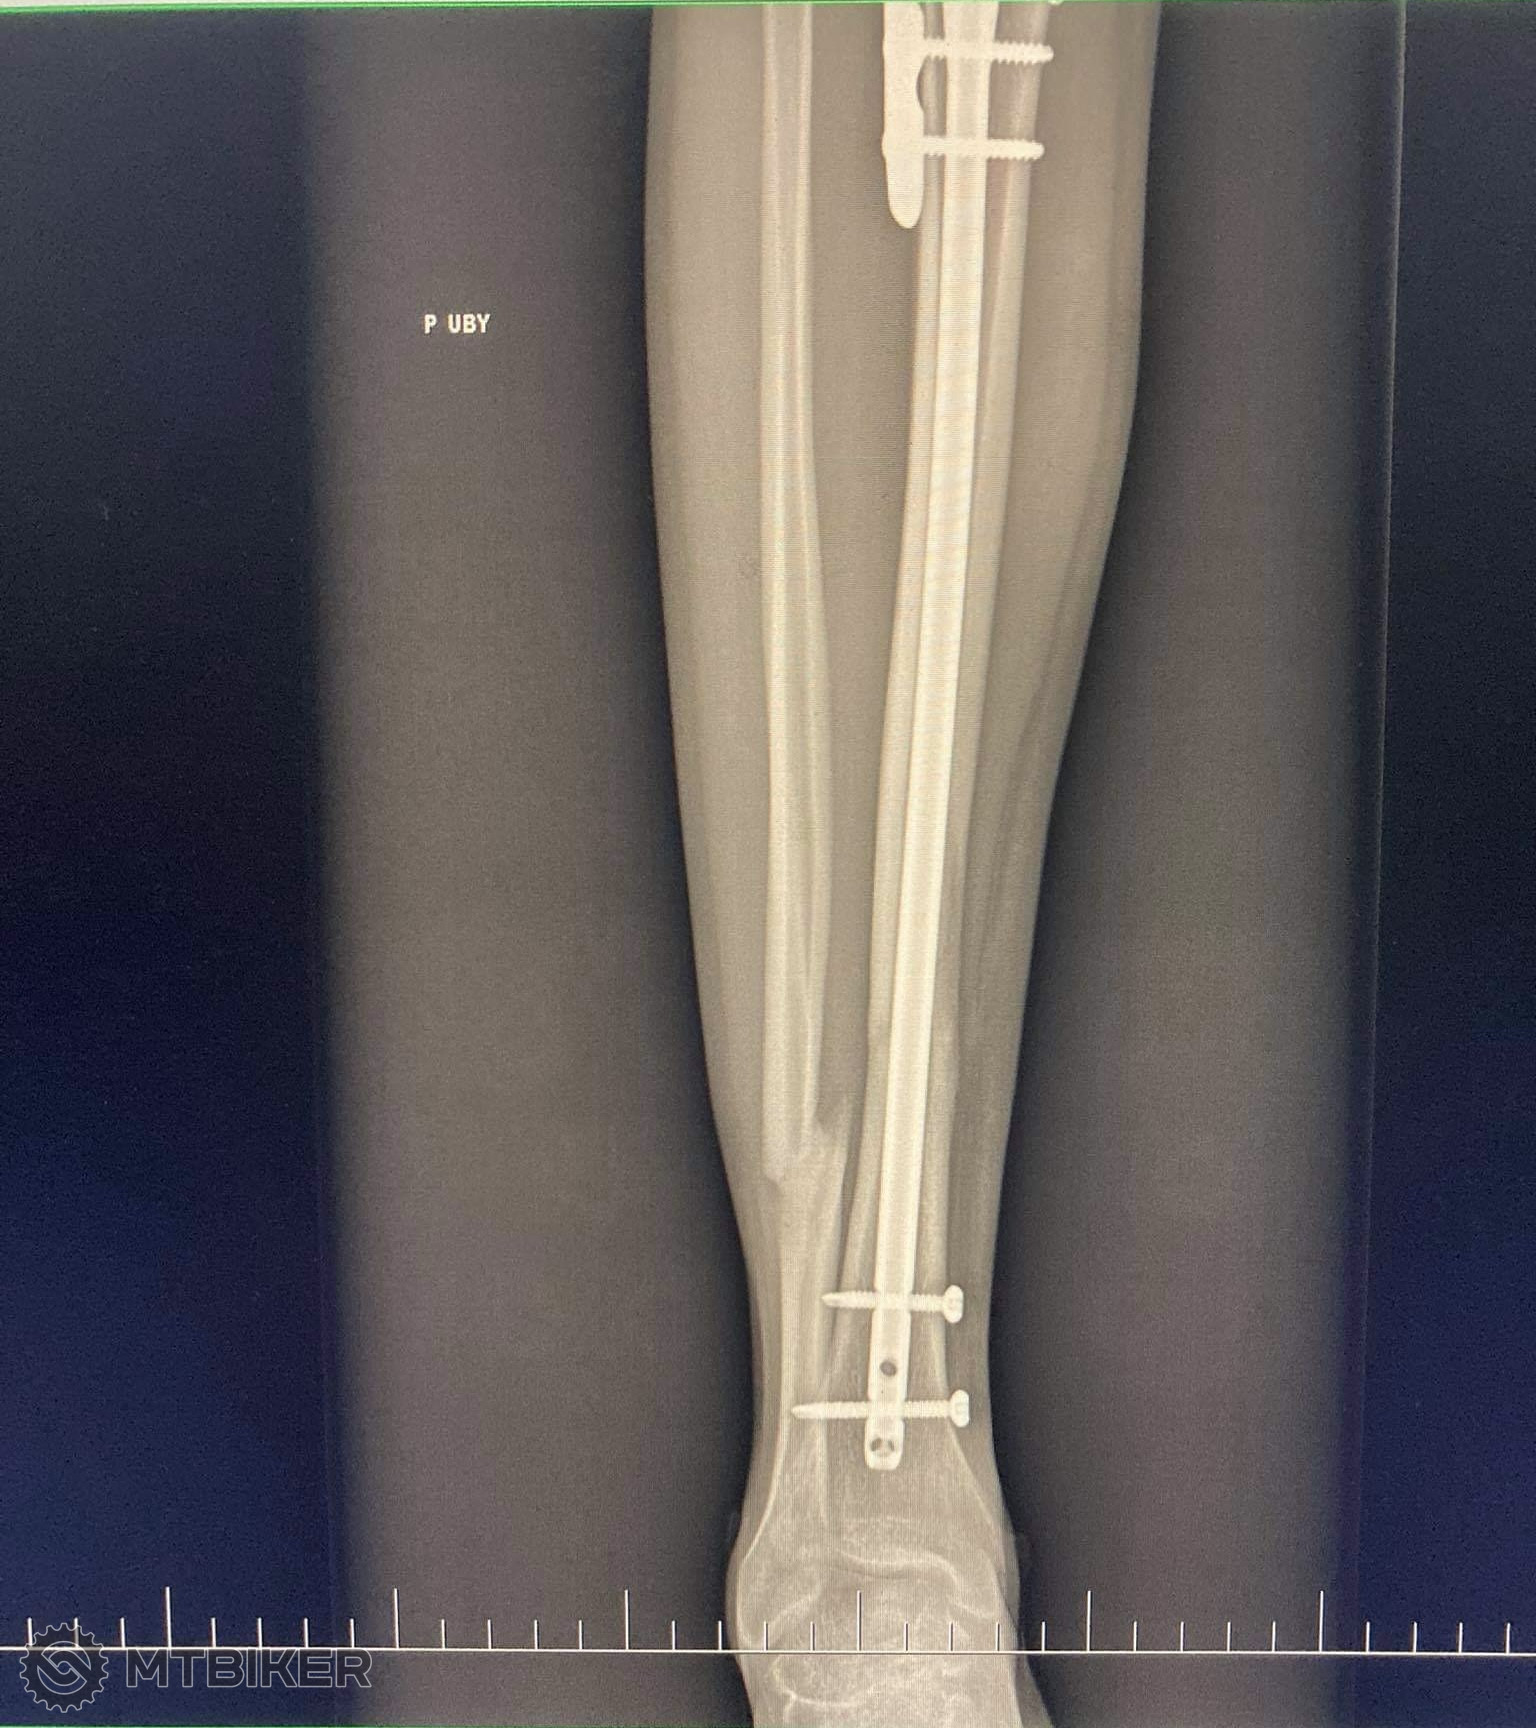

Kaper ta snimka rtg napravo na monitore to mas zlomeny krcok stehennej kosti ? Ako sa ti dari, ako sa to hoji?

Snimka potvrdila zlomeny krcok stehennej kosti... V ten isty den operacia - mali mi tam dat 2 sroby, snimok som este nevidel - bude pri dalsej kontole.

Pokial viem tak krcok nemam zlomeny,len to hentak zmontovali nejako.